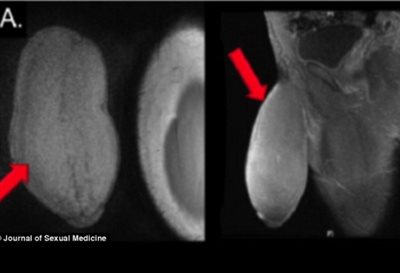

Σε επέμβαση συρρίκνωσης πέους υπεβλήθη ένας Αμερικανός 17χρονος έφηβος επειδή το γεννητικό του όργανο ήταν υπερβολικά μεγάλο και τον εμπόδιζε να κάνει σεξ και να συμμετέχει σε ορισμένα αθλήματα.

Το πέος του έφηβου είχε διάμετρο 25 εκατοστά και μήκος 17 εκατοστά. Οι χειρουργοί του περιγράφουν το σχήμα του σαν μια μπάλα αμερικανικού fotball.

Οι χειρουργοί δεν έκαναν τις τελικές μετρήσεις στο πέος του, παρόλο που ο ουρολόγος Δρ. Καρριόν δήλωσε ότι το αποτέλεσμα ήταν "γενναιόδωρο". parapolitika